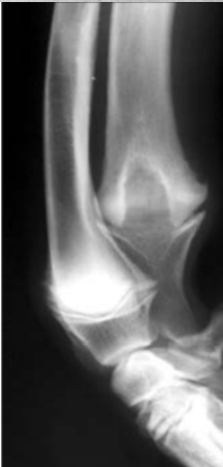

What does this depict?

Premature closure of growth plate distal radius.